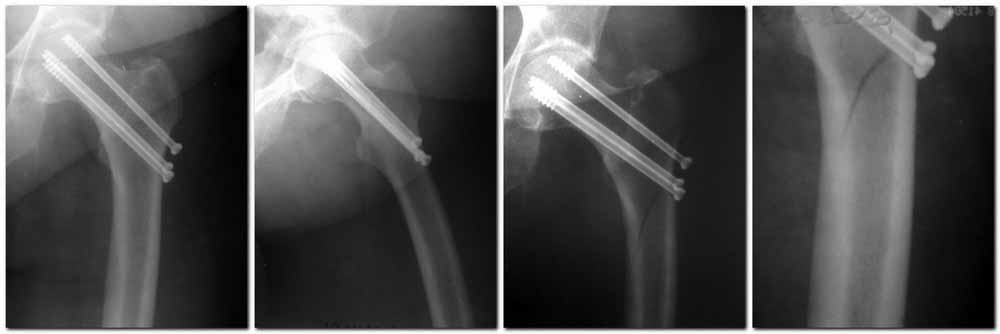

Пациентка Ш. 76 лет, 11 дней назад прооперирована по поводу вколоченного субкапитального перелома шейки левой бедренной кости, 3-мя канюлированными винтами. Вчера пациентка упала в палате. И вот результат- подимплантатный подвертельный перелом левой бедренной кости.

Уважаемые коллеги, пожалуйста посоветуйте какой метод дальнейшего лечения предпринять дальше.Соматически пациента повышенного питания, страдает варикозной болезнью нижних конечностей.Из предложенных вариантов коллег - целллокастовая укороченная кокситная повязка, скелетное вытяжение сроком на 40-45 суток - отпали сразу, так как необходимо активизация пациентки.На данный момент рассматриваем следующие варианта реостеосинтеза:(наличие технических возможностей)

1. Длинная Gamma 3 Stryker (с предварительной интраоперационной фиксацией головки спицами).2. Трохантерный штифт DePuy с 2-мя метафизарными винтами в проксимальном отделе, (также с интраоперационной фиксацией головки спицами.

Очень настораживает стабильность фиксации с проксимальном отделе с связи с выборкой костной ткани ранее находящимися там канюлированными винтами.

Сейчас пациентка находится на скелетном вытяжении, с дисциплинирующим грузом. Операция планируется после праздников.

Заранее извиняемся за качество и неполное соответствие проекций на R-ммах (R-служба отдельная песня). При интраоперационном ЭОП-контроле винты в аксиальной проекции разнесены по шейке.